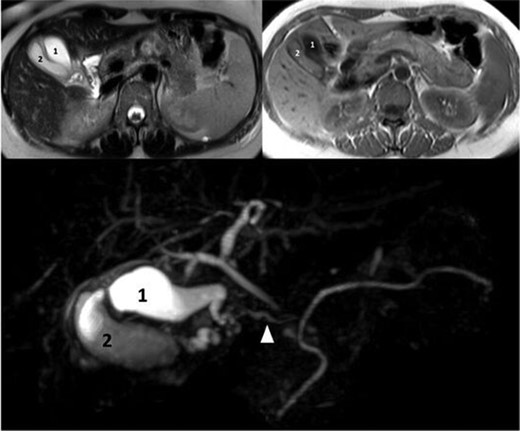

A 39-year-old healthy female, presented to our emergency department due to abdominal pain, nausea and vomiting. She was febrile, with a tender right hypochondrial and epigastric region. Her laboratory results showed a normal complete blood count and C-reactive protein level. Liver function test showed an elevation in total bilirubin at: 42 mmol/L, direct bilirubin level at: 29 mmol/L, gamma-glutamyl transferase (GGT) level at :160 U/L and Lipase level at: 34 000 U/L. An abdominal US showed two separate gallbladders with a sludge (Fig. 1). Abdominal CT scan showed a Balthazar grade C pancreatitis and confirmed the presence of a double gallbladder (Fig. 2). An MRCP confirmed the double gallbladder (Fig. 3). An ERCP was performed with evacuation of biliary debris in the common bile duct (CBD). The patient was discharged home after appropriate medical treatment a couple of days later with a full normal liver function test. Two months later, a laparoscopic cholecystectomy was performed where the two gallbladders were dissected with a dome-down technique, from the gallbladder fundus towards the neck (Fig. 4), the cystic duct and artery were identified. An intraoperative cholangiography was performed which showed patent intrahepatic ducts, cystic and CBD (Fig. 5). A Hem-o-lock® clip (WECK Closure System; Teleflex Inc., Morrisville, NC, USA) was then placed on the main cystic duct (Fig. 6), and another Hem-o-lock® clip was placed on the cystic artery. Figure 7 showing the gross specimen. The final histopathology report concluded two separate gallbladders, each having its own cystic duct, with both cystic ducts joining to form a main cystic duct.

MRI with T2-weighted, T1-weighted images and MRCP showing two distinct gallbladders and one main cystic duct (arrowhead).